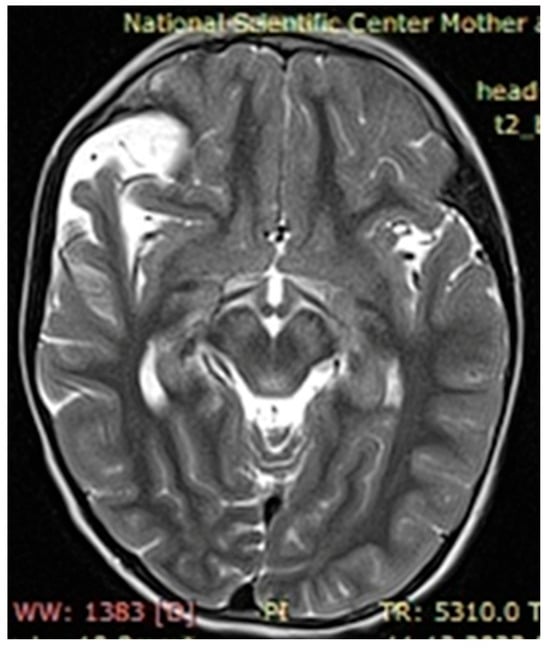

The observed café au lait macules originated in the early childhood of our patients and in most cases grew as they approached adolescence. Around 60% of patients with neurofibromatosis had two, simpler neurofibromas, characterized by nerve hypertrophy, which in turn caused displacement of adjacent tissues, organs, and bones if located next to the pelvis and/or spinal cord. There were several patients presenting with severe cases of scoliosis, lordosis, and torsion of the rib cage due to ongoing growth of neurofibromas, identified via MRI as focal areas of increased signal intensity, with space-occupying lesions verified on the T2-MRI STIR (Short Tau Inversion Recovery) regime as plexiform neurofibromas.

Upon further growth of neural tissues, patients presented with plexiform neurofibromas, located around the eye tract, neck, spinal cord, and groin (examples presented in Figure 3, Figure 4 and Figure 5). A total of 14 patients presented with optic nerve and optic tract glioma as well as retinopathies, retinal angiopathies, declined vision, astigmatism, and other eye pathologies. Many patients complained that eye plexiform neurofibroma occluded their vision, causing gradual vision loss due to lack of accommodation and increased tissue growth.

Figure 4. Case 2, clinical diagnosis of a 12-year-old boy: neurofibromatosis type 1, plexiform neurofibroma of the left periorbital region, mild truncal ataxia, and mild dysmetria. With single nucleotide replacement variant NF1 Chr17 NM_000267.4:c.5792G>A.